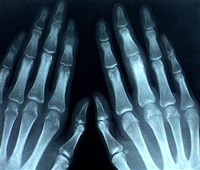

Рентгенологическое исследование основано на особом свойстве рентгеновских лучей проникать через плотные непрозрачные среды и поглощаться ими в неодинаковой степени в зависимости от их химического состава и физических свойств. В результате на светочувствительном экране, воспринимающем рентгеновские лучи, прошедшие через участок человеческого тела, получают плоское теневое позитивное изображение внутренних органов человека без нарушения целостности кожных покровов. Различные органы и ткани дают на экране тени неодинаковой интенсивности, что и создает возможность отличить их друг от друга. Например, на фоне прозрачных для рентгеновских лучей легких можно исследовать сердце (размеры, положение), определять воспалительные участки в легких и др. Особенно успешно прямое рентгенологическое исследование применяется при диагностике целостности костей скелета, т.к. костная ткань в наибольшей степени поглощает рентгеновские лучи и очень хорошо контрастируется на фоне остальных тканей человеческого тела.

При проведении прямого рентгенологического исследования обычно сначала получают изображение просвечиваемого участка тела на светочувствительном экране (рентгеноскопия). При этом врач имеет возможность расположить человека относительно источника излучения таким образом, чтобы изображение исследуемого органа было наиболее информативным с диагностической целью. Затем изображение фиксируется на светочувствительном материале (рентгенография) для дальнейшей расшифровки и документирования проведенного исследования.